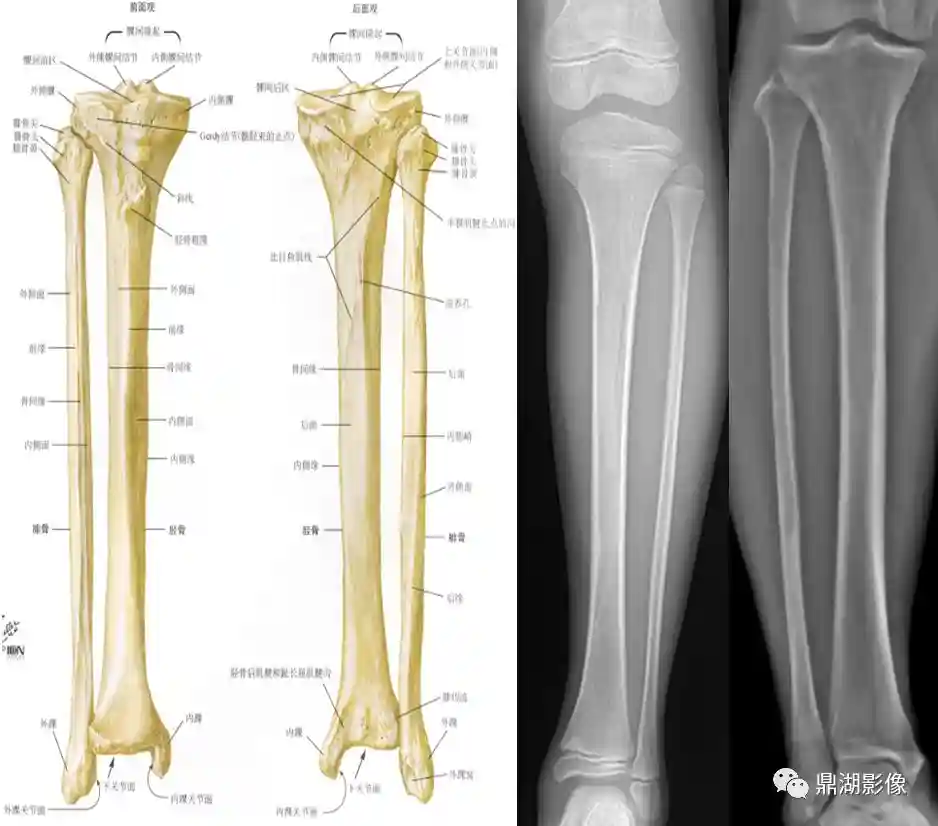

胫骨、腓骨

胫骨:位于小腿内侧,分一体两端,上端膨大,向两侧突出,形成内外侧髁;下端稍膨大,其内下有一突起为内踝

腓骨:位于胫骨外后方,分一体两端,上端稍膨大为腓骨头,下端膨大形成外踝